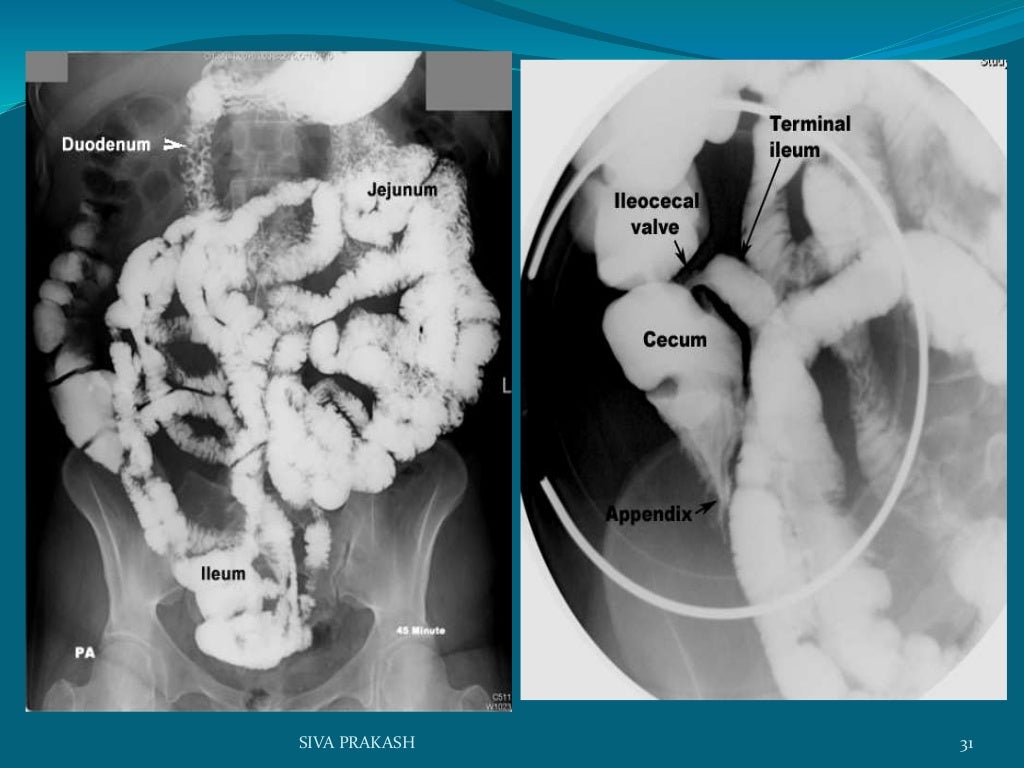

BARIUM MEAL FOLLOW THROUGH (BMFT) Endoscopy Barium Meal a barium meal is an examination of your stomach and your oesophagus (or gullet); a barium meal is a diagnostic test used to detect abnormalities of the esophagus, stomach and small bowel. This uses a flexible telescope to look into the. the main alternative to a barium swallow and meal is a gastroscopy (also called an endoscopy).. Endoscopy Barium Meal.